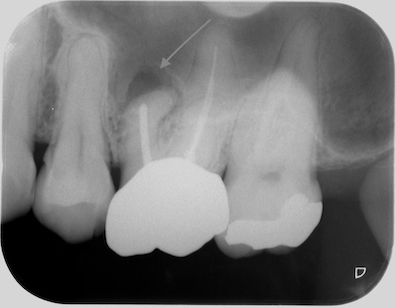

術前のレントゲン写真です。

診査の結果、根の先に炎症があり(レントゲン写真の→で示した黒い部分)、根管治療をすることになりました。

レントゲン写真から、根の先に炎症がある根は曲がっており、曲がった先まで治療ができていないように見えました。さらに、以前に治療をした先生が、曲がった方向ではなく、まっすぐに根を大きくし、変な方向に穴を空けてしまっているようでした。おそらく、パーフォレーションが起きています。